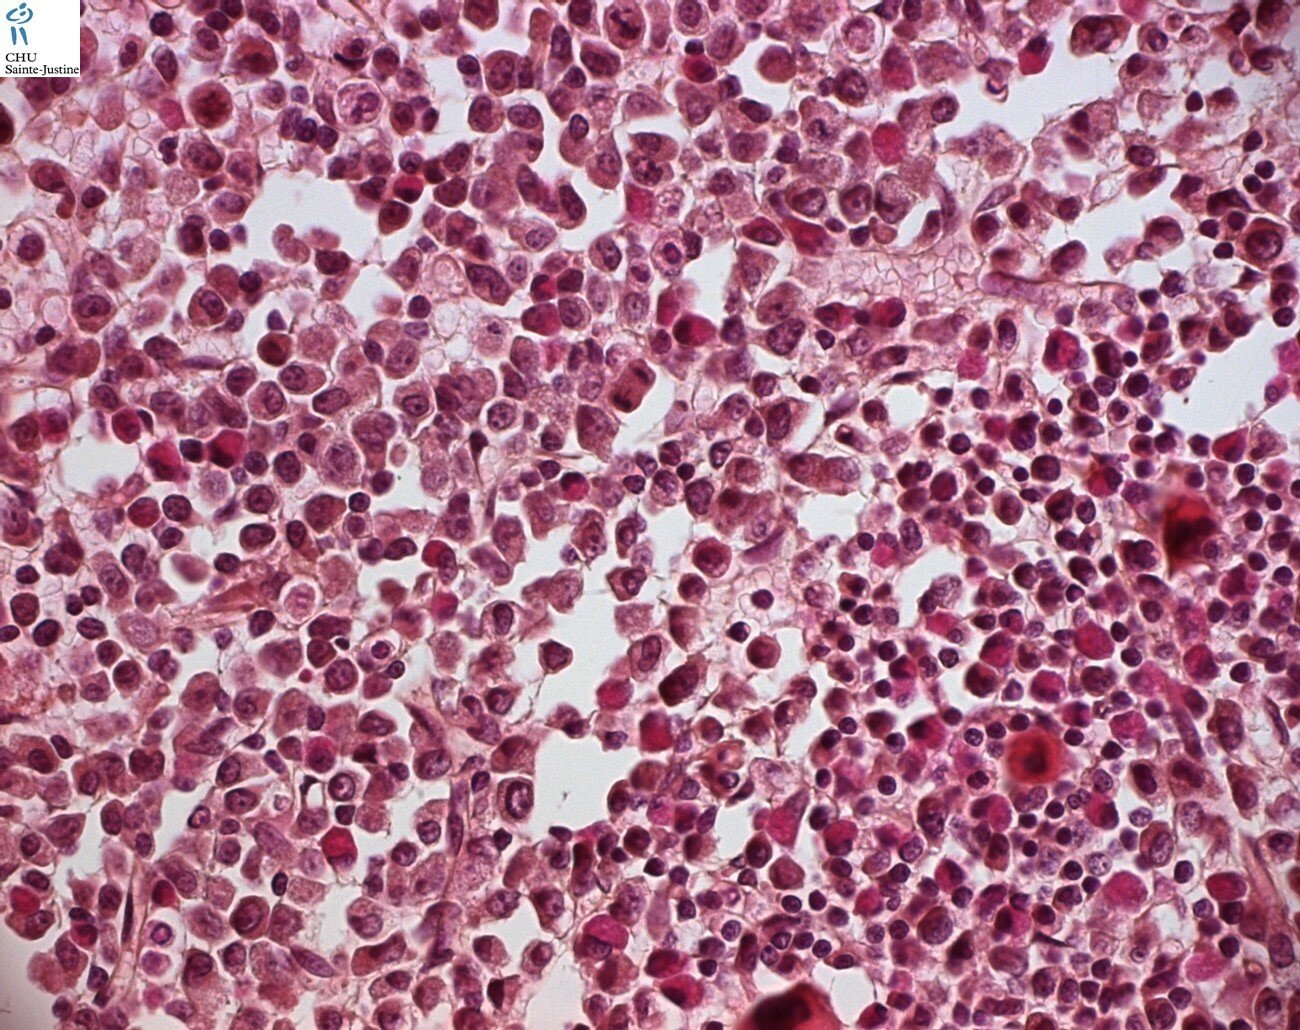

Morphology